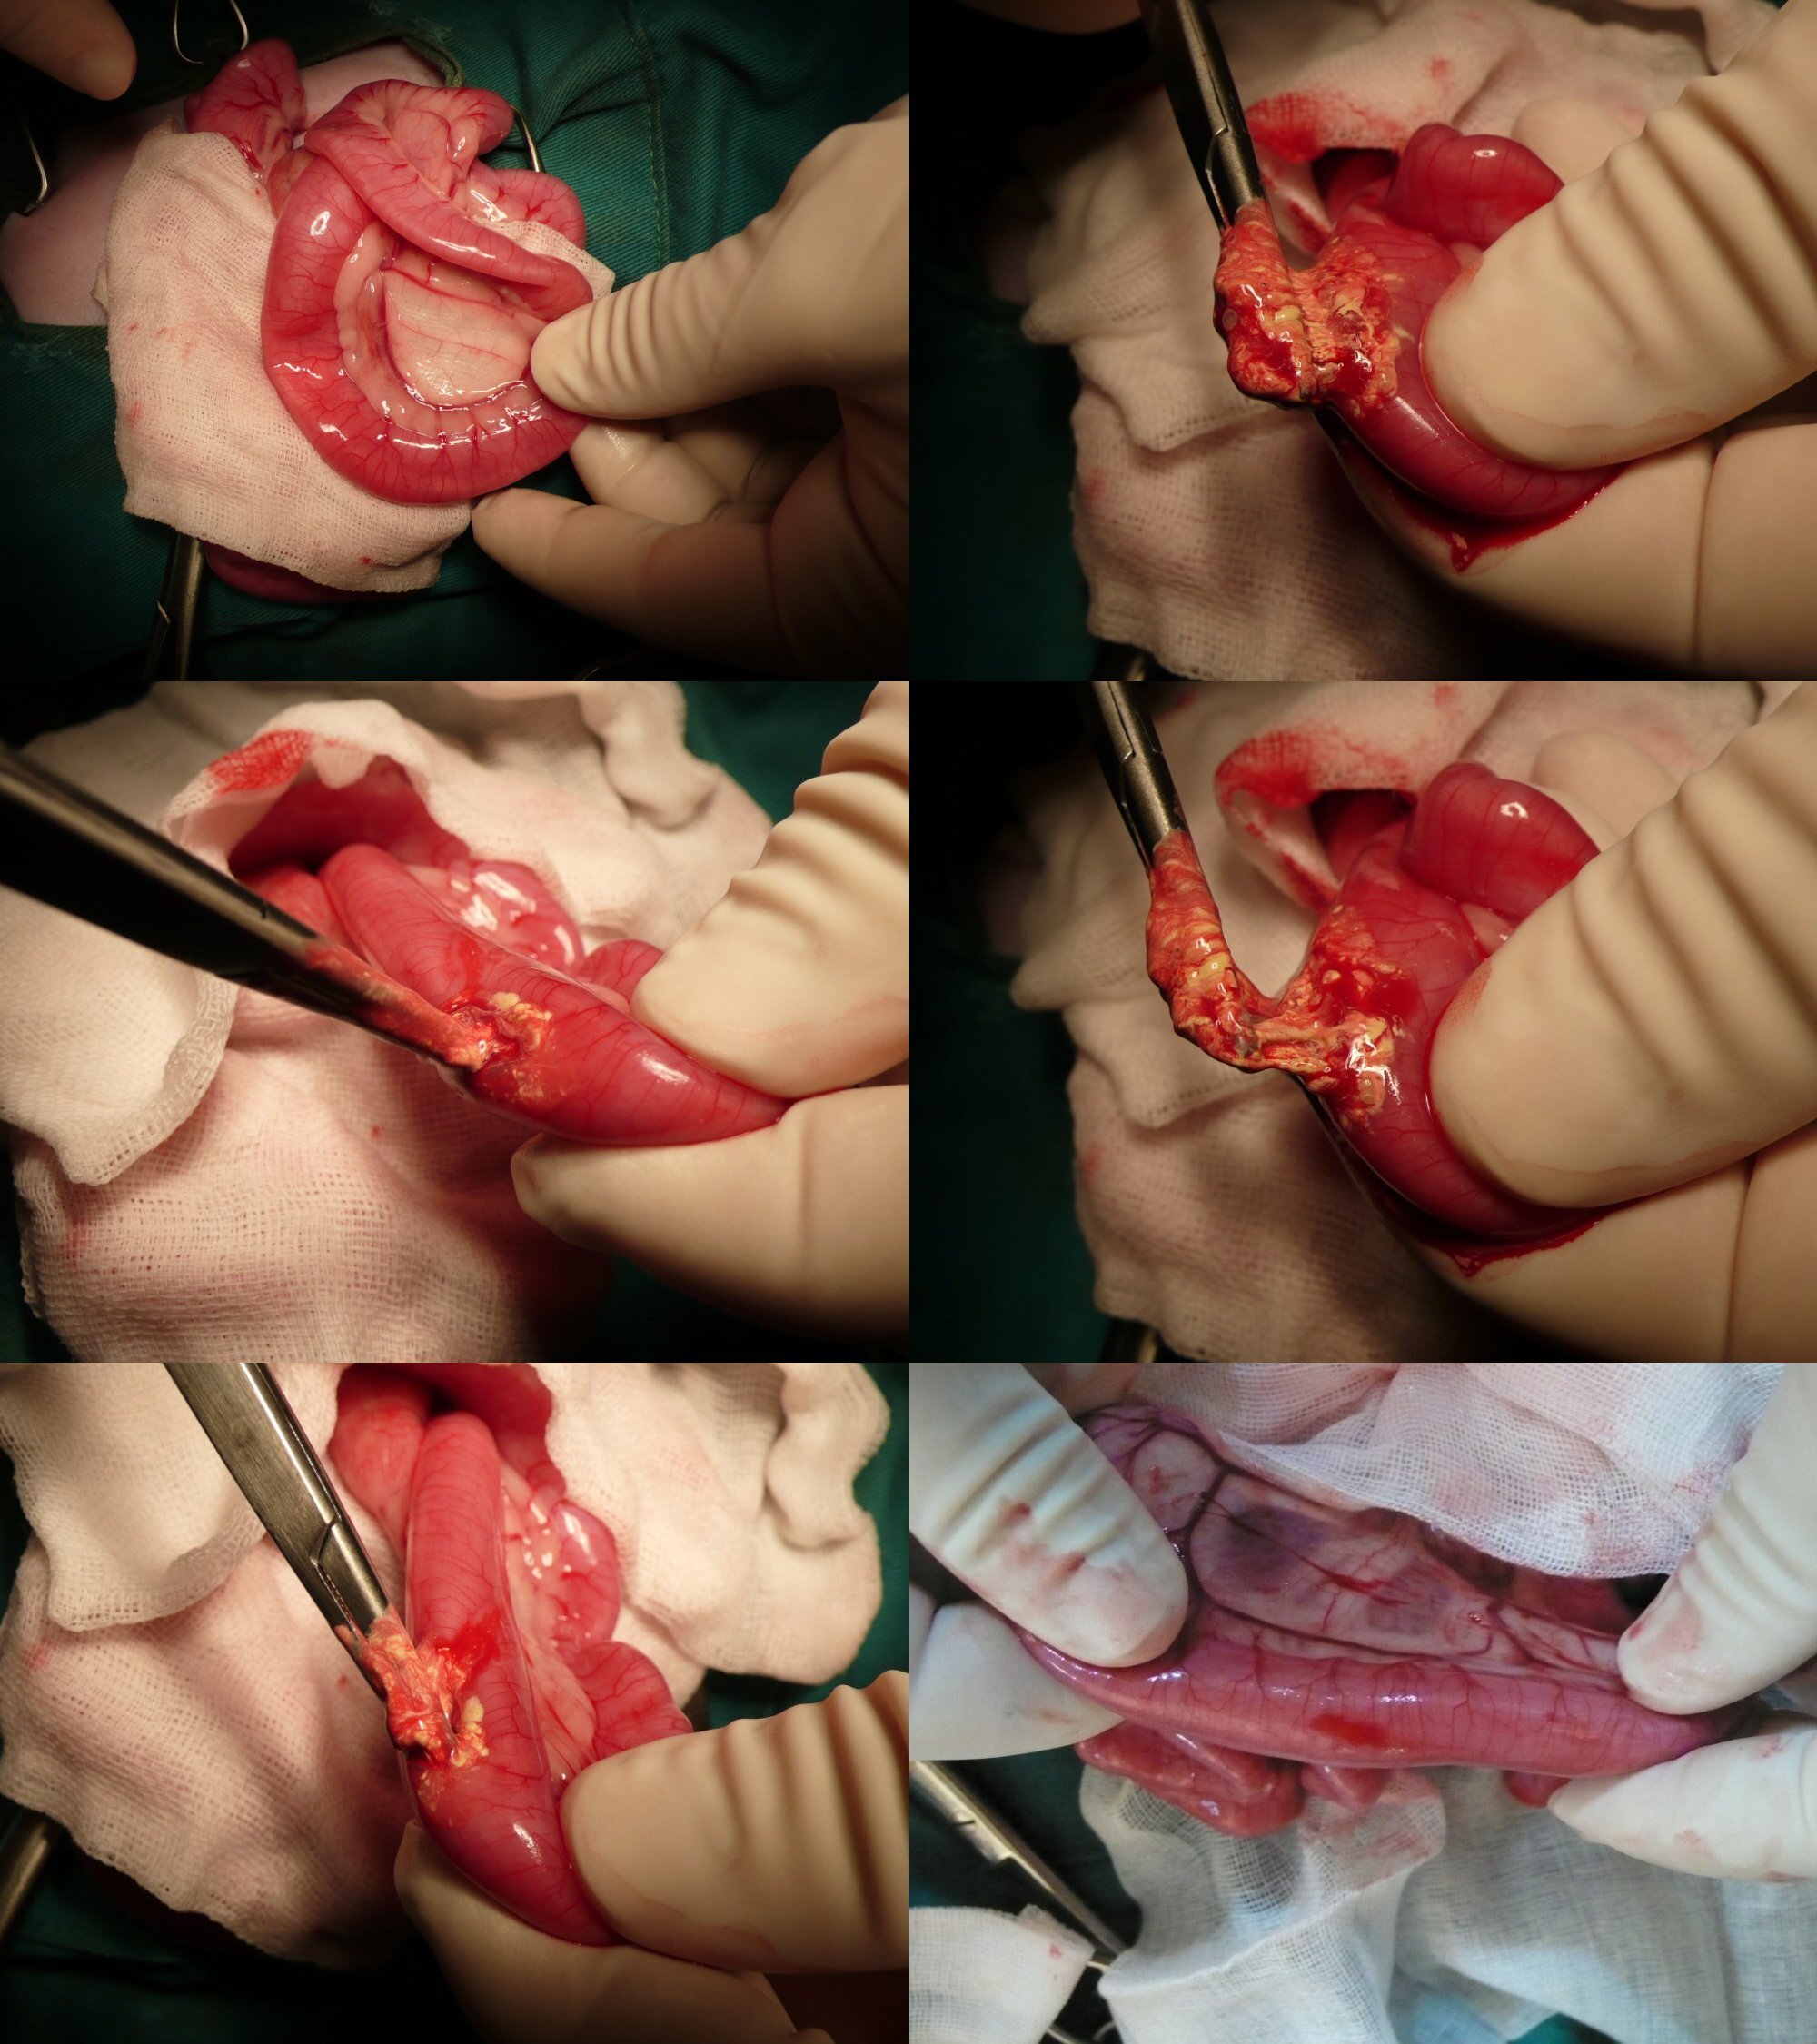

經過X光造影發現,腸內有異物阻塞,應是無法進食及嘔吐主因,經手術後取出類似粘土的不明物體,阻塞在腸內,原以為手術後應會很快恢復健康,但貓還是每天躺著,且有呼吸道感染,需做噴霧治療,無法自行進食,需以人工餵食,但可以明顯發現貓展現出他想進食的本能,只是無法自己起身吃東西,而進食後的嘔吐現象也沒有了,這期間做了血液檢查、細菌培養等,都呈現正常反應,但貓卻像一點力氣也沒有般的只能躺著,經過投以肌力無力症葯物,還是不見效果,貓最後因腦性麻痺導致全身肌肉無力,最後呼吸肌肉衰竭而離世。